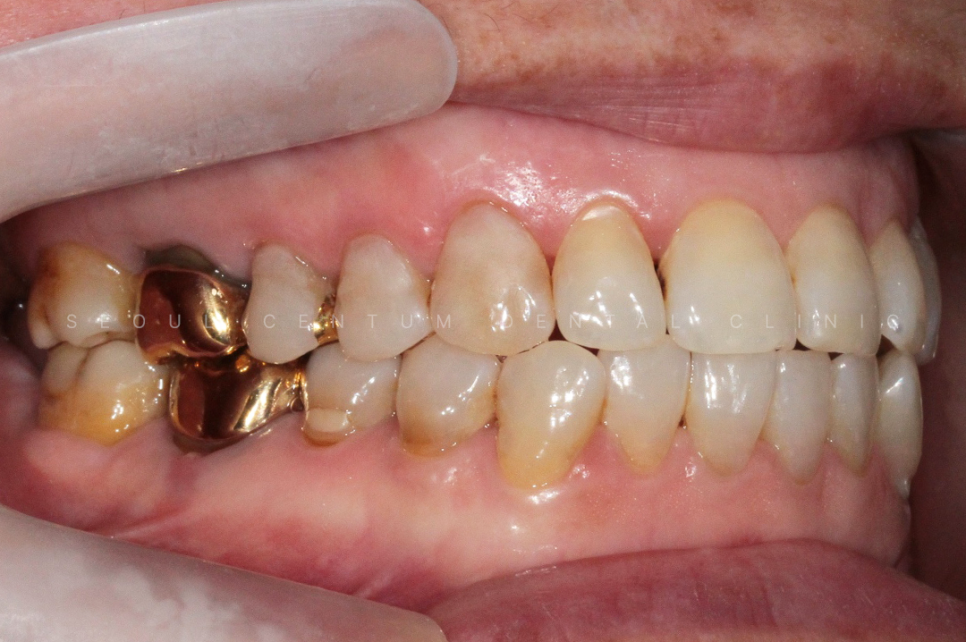

아래 사진은 실제 서울센텀치과에

치경부마모증이 뭔지 모르는 상태로

내원하셔서 치료를 하게 된 케이스인데요.

60대 여성으로 동네에 치과에 스케일링을

오랫만에 하러 갔다가

치아가 파였다는 말을 듣고

거울을 보고나니 치아가 보기 싫어져서

라는 이유로 내원을 하셨어요.

실제 육안으로 봤을 때도 크게

치경부마모증이 진행된 부분이 많았고

당일에 바로 진행을 하게 되었습니다.

크게 진행이 된 8개의 치아를 진행하기로 했고

강도가 강한 레진으로 진행해 오래

유지를 잘 해보시기로 이야기가 되어

레진으로 진행을 했습니다.